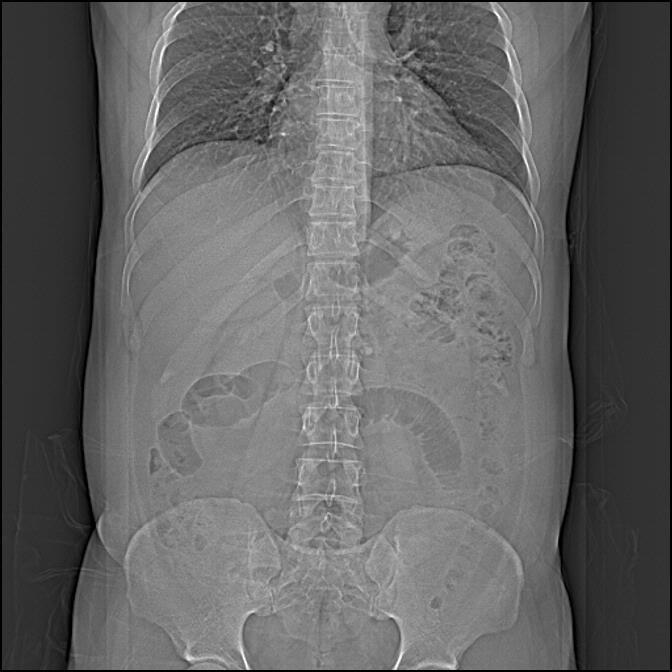

Scenography shows “sentinel loop” sign in the left lower quadrant. Enhanced axial CT demonstrates an ovoid inflamed fatty mass (arrow).

Omental infarction has a clinical presentation similar to that of epiploic appendagitis, with the infarcted fatty tissue being a segment of the omentum. CT demonstrates an ovoid inflamed fatty mass, larger than in epiploic appendagitis and lacking a hyperdense ring on CT [1].